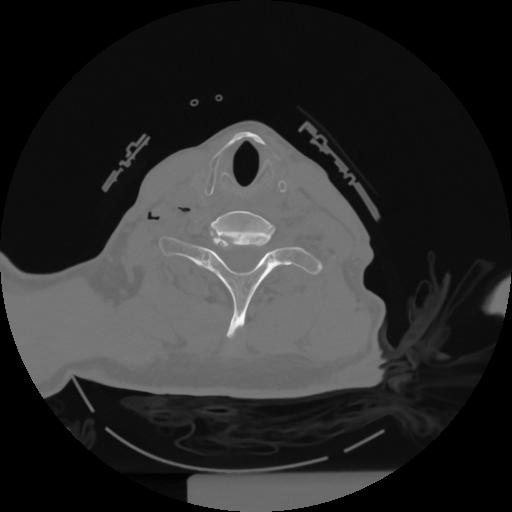

12 P.BLANDAS,,Vol,0.5,P.BLANDAS,,